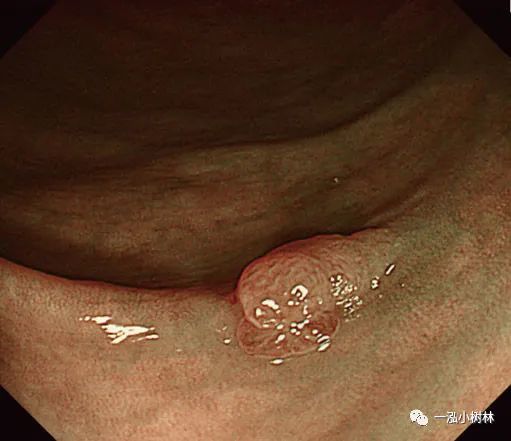

例5 小息肉冷圈套切除术

图5a 横结肠处4mm大小0-IIa型腺瘤

图5b 在病灶上方圈套

图5c 圈套包括病灶周围1-2mm正常黏膜